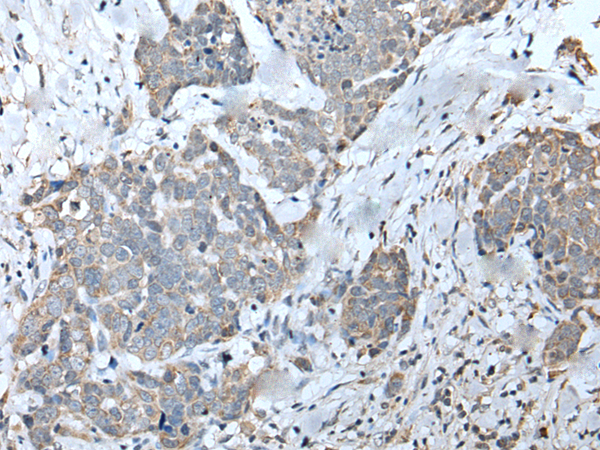

IHC positive control: |

Human cervical cancer |

IHC Recommend dilution: |

20-100 |